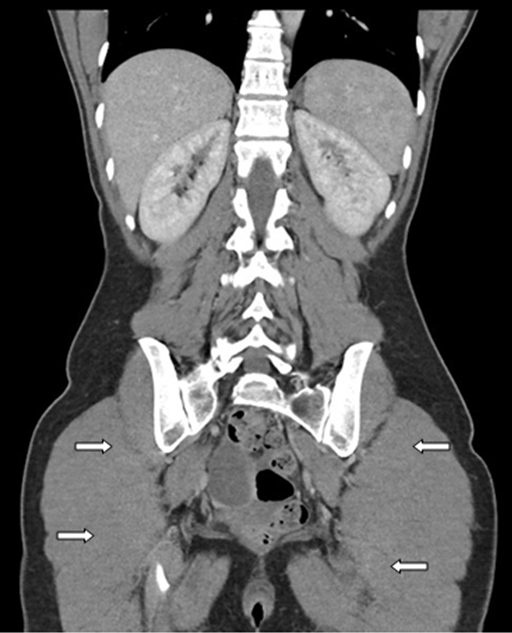

A 41-year-old female, para 2, admitted to hospital for right iliac fossa pain, plus reduced appetite and weight loss, that had been present for two months. Furthermore, the patient had generalized tenderness in lower abdomen. Observations showed normal blood pressure and pulse, but raised temperature of 37.8°C. Computed tomography scan revealed bilateral predominantly cystic ovarian masses with solid component, plus multiple peritoneal nodules with pelvic free fluid (Figure 1) and (Figure 2). Ultrasound of the abdomen and pelvis showed a normal-sized anteverted uterus with an IUCD in situ within the endometrial cavity. It confirmed earlier CT scan findings regarding bilateral complex adnexal cysts; measurements were 70x63x61 mm (right) and 63x48x54 mm (left). The right ovary was separate from the cyst, but the left ovary was not separate from the adnexal cyst. White cell count and C-reactive protein results were only slightly raised 13x109/L and 119 mg/L respectively, and tumor markers CA125, CEA and CA19-9 were normal.

Figure 1: Axial computed tomography imaging of patient, upon admission to hospital. The bilateral cystic ovarian masses are visualized and the IUCD can be seen in the endometrial cavity.